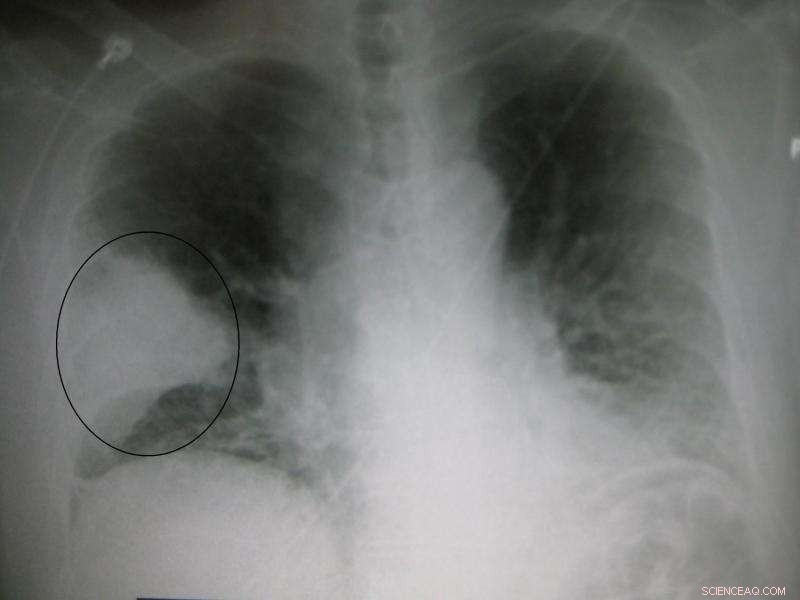

A black and white X-ray picture showing a triangular white area on the left side. A circle highlights the area. Credit: James Heilman, MD./Wikipedia